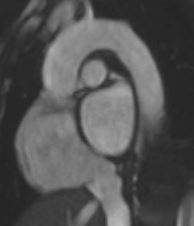

LVOT View